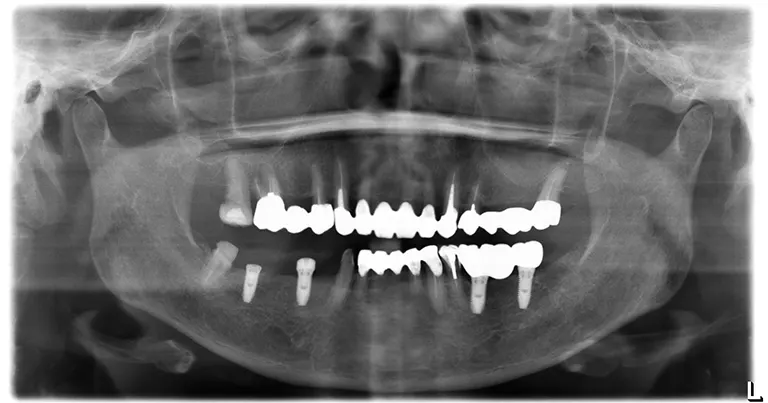

• After インプラント治療後の状態

インプラント埋入

右下顎臼歯部にインプラントを埋入した後のレントゲン写真です。

(左側は先にインプラント埋入していた為最終的な被せ物が装着された状態です。)